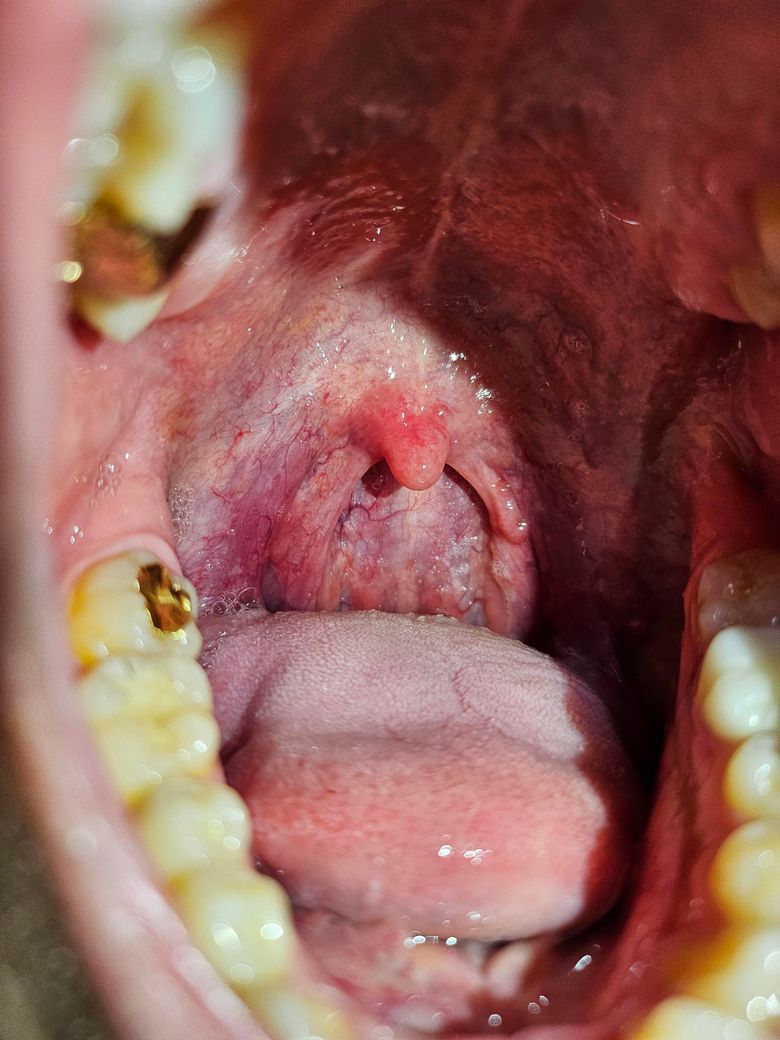

인두쪽에 혹같은게 낫는데 확인바랍니다.

사진상으로 보시면 오른쪽에 인두에 울퉁불퉁하게 왼쪽인두랑 다르게 뭔가 솟아있고 인두벽에 붙은거같은 느낌인데 괜찮은건가요? 확인부탁드립니다.

올려주신 사진에 특별한 이상 소견은 저명하게 관찰되지 않으나 직접 육안적 관찰 소견과는 차이가 있을 수 있으므로 걱정이 되시면 이비인후과 진찰을 받을 것을 권합니다.